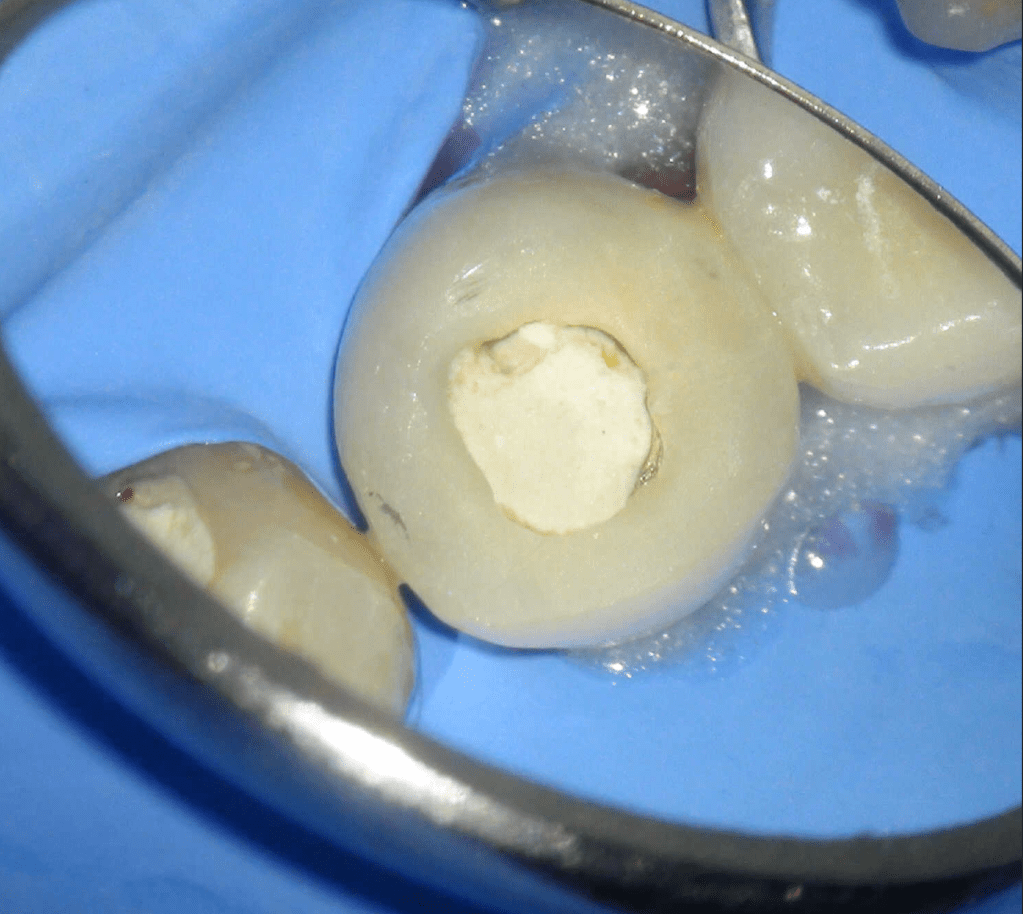

Molar superior

Reco palatina

Reco pared vesticular

Reco pre-endo gingivectomái, pared yuxtaosea

Reco pre-endo, molar inferior

Reco preendo + 4 conductos molar superior

Reco preendo + gingivectomía

Reco preendo, 2o Molar superior

Reconstrucción debajo de puente